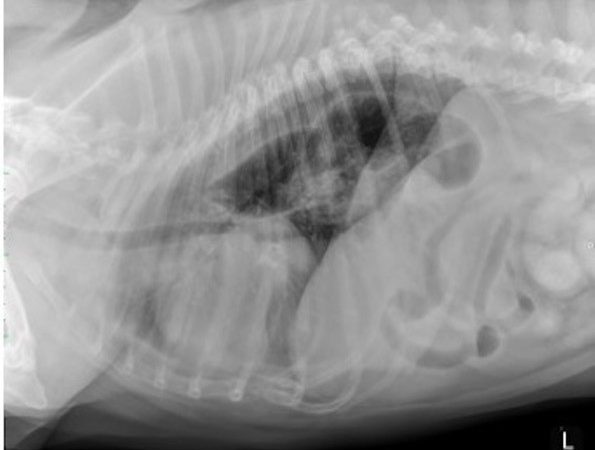

Our radiography reading sessions are a great way for our Specialists to bring new and interesting diagnostic imaging conundrums for discussion with our vtx community. In this session, the theme is thoracic imaging in small animals.